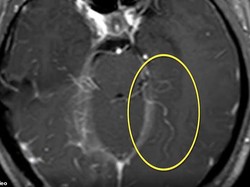

Hobi Makan Daging Mentah, Otak Wanita Ini Dipenuhi Cacing Hidup

Seorang wanita di China harus dilarikan ke rumah sakit setelah otaknya dipenuhi cacing. Gara-gara ia sering konsumsi daging mentah.